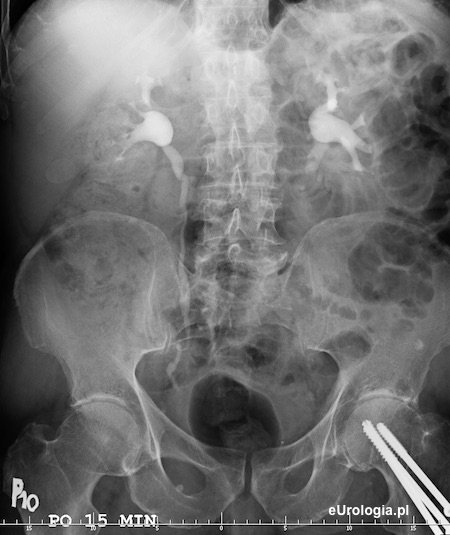

Zdjęcie urograficzne wykonane po 15 minutach - widoczne zakontrastowanie układów kielichowo-miedniczkowych obu nerek oraz górny i środkowy odcinek prawego moczowodu